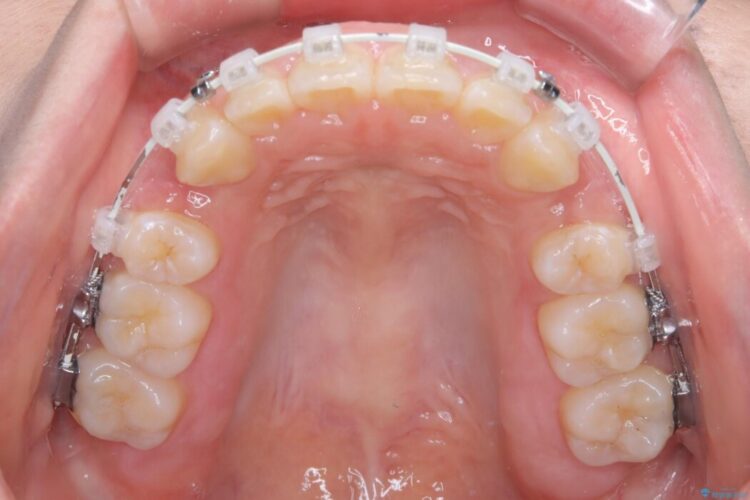

- 矯正装置:ワイヤー(審美装置)

矯正検査の結果、前歯が外側に強く倒れ込んでいる「唇側傾斜(しんそくけいしゃ)」が認められ、口元の突出感の原因になっていました。

この傾斜を根本から正し、前歯を十分に後方へ下げるスペースを確保するため、上下左右の4番を抜歯し、目立ちにくい審美ワイヤー装置にて治療を行うこととしました。